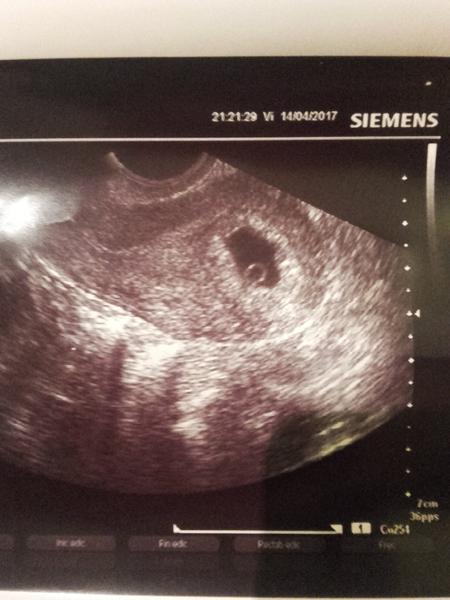

@karmela ahoj, prepac, ze sa miesam do diskusie..ja som bola dnes na pohotovosti..som presne 5+4 a foto takato..embryjko ma 1,9mm ale vravela, ze maju slabe sono, ze preto tak zle vidiet..ze na jej v ambulancii by uz bolo lepsie..

@amelie2017 ahojky nie vôbec nevadí že sisa pridala do diskusie krásne vidieť na fotke už miminko 😍 Čo si mala nejaký problém že si bola na pohotovosti? Želám ti pekne a bezproblémové tehulkovanie 😊 Takze mám šancu že bude vidieť miminko 😃Ďakujem za info

@amelie2017 ja som dnes 5tt+2 ale k doktorke som objednaná až na 26.4. :/ Dúfam, že teda aspoň už bude niečo vidieť ako tebe 😊 Gratulujem a užívaj si 😊